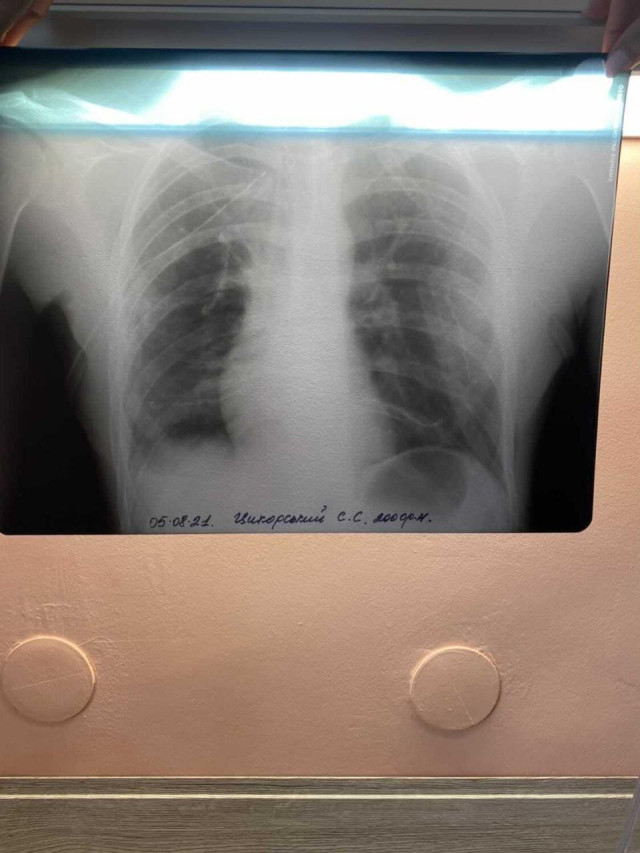

Про це Інформаційному агентству Волинські Новини повідомив Семен Цикорський. Ще у 2018 році у хлопця діагностували синовіальну саркому м’яких тканин правого плеча з метастазами в легенях четвертої стадії. Наразі Семен проходить лікування, йому рекомендована операція на легені. Згідно з останнім обстеженням від 25.06.2021 його стан погіршився. Раніше на сайті йшлося про те, як Семен приймав таблетовану хімію «Вотрієнт». Ліки дали результат, після чого йому продовжили ще на 3 місяці приймати цей препарат. Стан став стабільний. Семену припинили таблетовану хімію на три місяці.До слова, 2 квітня 2020 року після чергового блоку хімії, у столичному інституті раку Семена приголомшили дивовижною новиною – метастазів у легенях немає. Усі аналізи ідеальні – тож хлопець абсолютно здоровий. Не повіривши такому щастю, молодий чоловік перевірявся ще раз, і ще раз, але в усіх клініках результат один – пацієнт Семен Цикорський абсолютно здоровий! Але 10 липня 2020 року під час чергової томографії лікарі виявили у Семена Цикорського метастази у легенях. Але навіть після цього молодий чоловік не опустив руки і пішов навчатися на чоловічого перукаря – барбера, і згодом влаштувався на роботу. Але не судилося. Стан здоров’я лише погіршувався.

Вже з 25 червня 2021 він поїхав в Національний інститут раку. Хірурги рекомендували онкохворому робити операцію на легені, на що хлопець погодився, а 4 серпня 2021 року його проперували у Національному інституті раку.